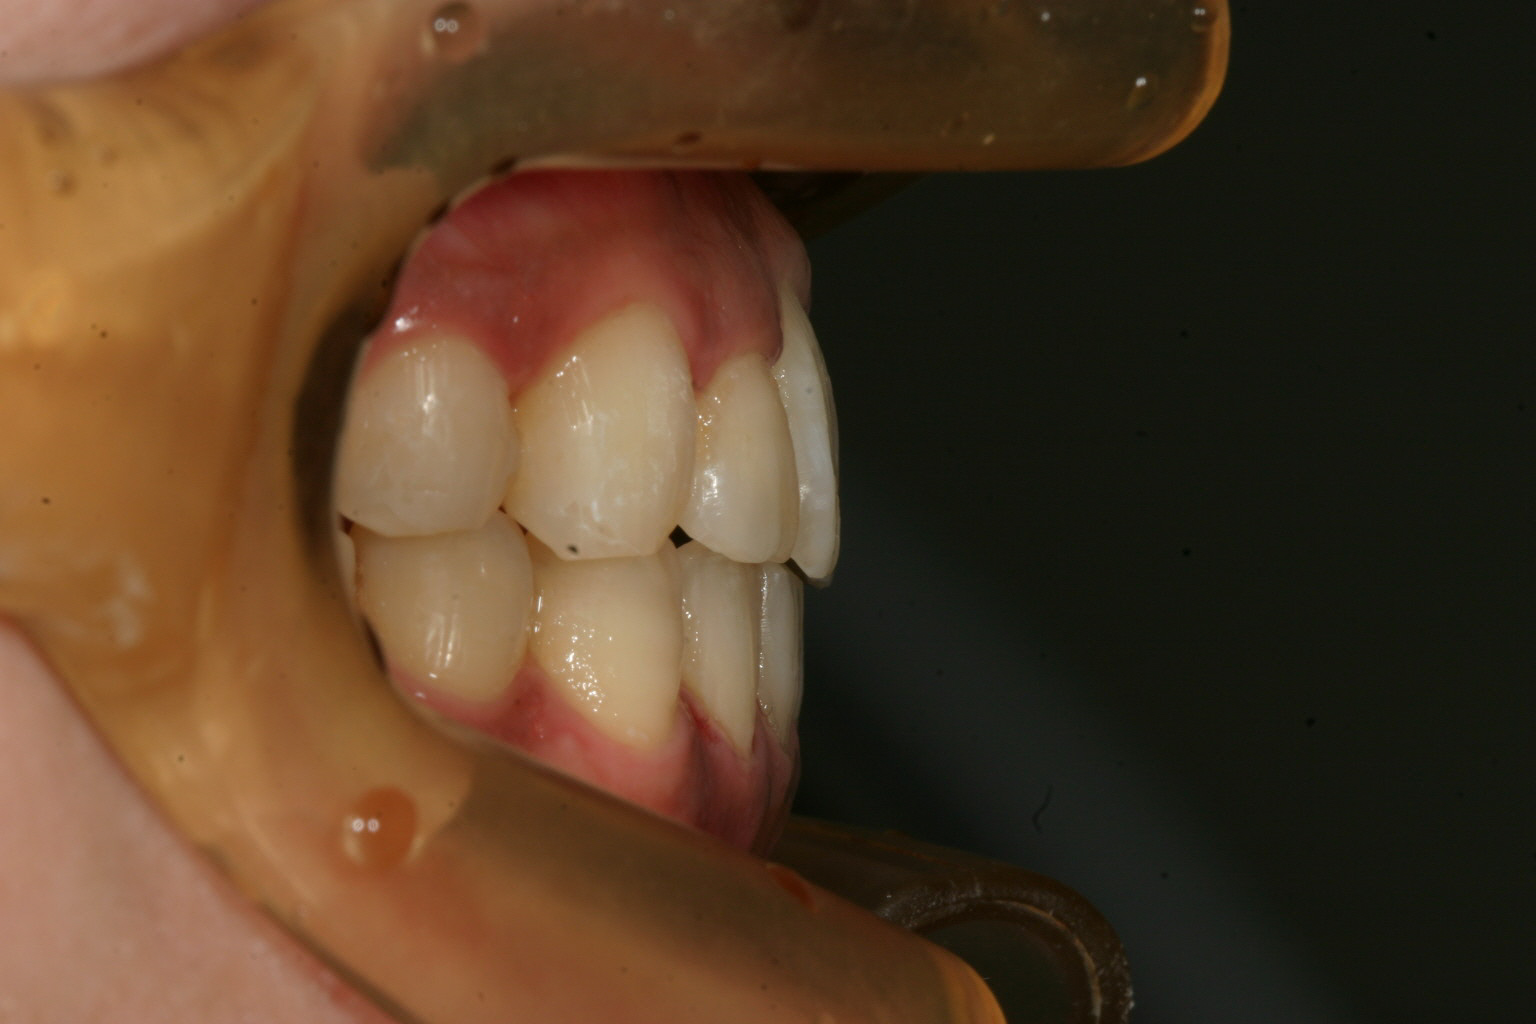

横から見た出っ歯感は前から見た感じより大した事無いですね!

綺麗に改善してますね~ 患者様がかなり頑張ってチューイ咬んで頑張ってくれました。

下顎もいい感じです。

前突感も最高です。